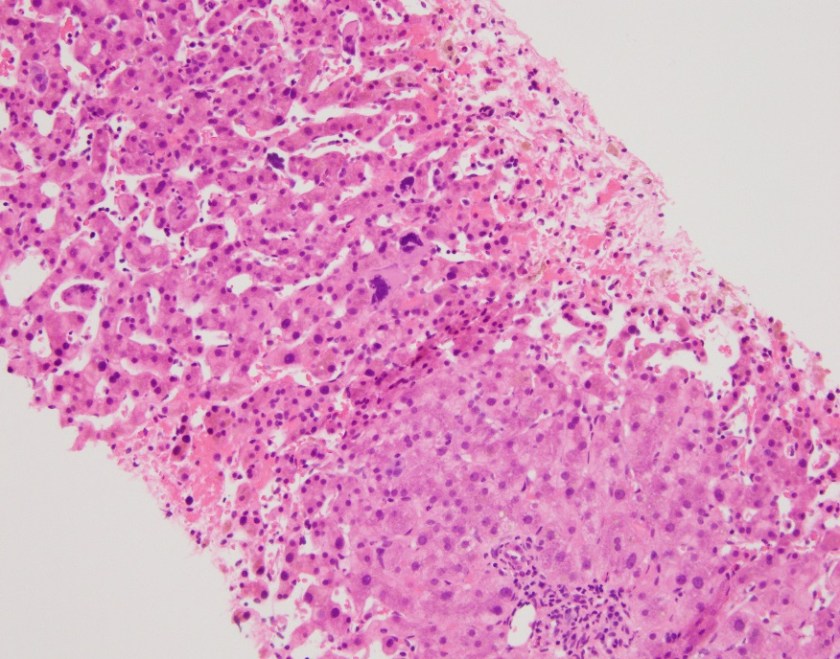

H&E stained sections reveal sheets of large lymphocytes. The lymphoid cells are medium to large in size with irregular nuclear contours and prominent nuclei. Areas of necrosis are prominent. No specific areas of epithelial ulceration are noted. Immunophenotypic characterization of the larger cells reveals positivity for CD20, CD30, CD79a, PAX5, MUM1, Epstein Barr virus encoded RNA (EBER) and a variable Ki-67 proliferation index, which is up to 60-70% in the larger cells, but around 20-30% overall. Only rare cells are positive for BCL-2 and BCL-6. The lymphoma cells are negative for keratin AE1/AE3, CD10, CD4, CD8, CD21, CD23, CD7, CD5, Cyclin D1, CD68, CD56, and CD43. The background T cells express CD5 and CD7 and are a mixture of CD4 and CD8 with CD4 predominance.